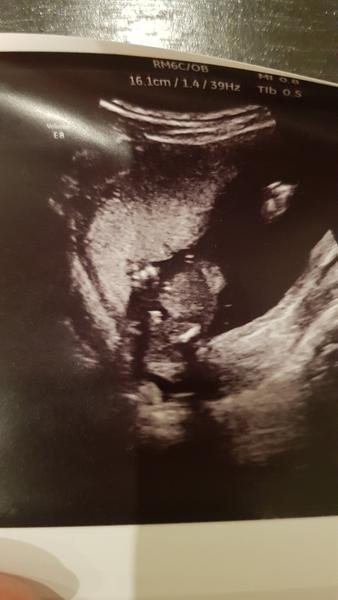

Dobry vecer, dámy, na fotce by měla být vybavicka naseho malýho v 17tt. Doktor si stále není jistý, vidí to spis na kluka, ale malý se dost schovává. Jaké jsou vaše názory? Moc si přejeme holcicku, tak trosku porad doufáme, ale samozřejmě platí "hlavně, aby to bylo zdravý!" 🙂 Díky za názory.

@klara666l lepší fotku prosím nemáš?

Vidim tam koalu. Nic vic. Vubec nevim, co tam je vyfoceny. Pockej si na priste

@kiki1912 Bohuzel, pak mam jen hlavicku. 😁☹